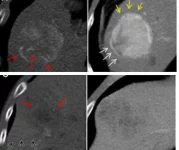

Гибридная компьютерная томографическая радиомика модель продемонстрировала площадь под кривой до 86 процентов при прогнозировании микрососудистой инвазии у пациентов с гепатоцеллюлярной […]… далее

Повреждения ремней безопасности в результате дорожно-транспортных происшествий могут быть изначально неправильно диагностированы, они могут быть опасными для жизни и требовать […]… далее

Согласно исследованию, опубликованному 28 марта в журнале «Радиология», импульсная радиочастота под контролем КТ в сочетании с инъекцией стероидов представляется многообещающей […]… далее